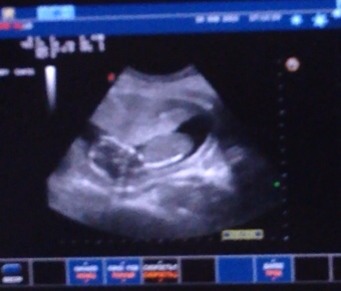

Девочки, я вся в расстроенных чувствах😔😔😔Сегодня с мужем решили заехать в платную клинику на узи, подумали, может пол нам скажут , так как следующее узи мне в жк назначали только через 3 недели , и я хотела , чтобы папа на него посмотрел ) Пришли на узи, а врач говорит у вас сильный гипертонус, вам его срочно снимать нужно, никакого пола вам не скажу сейчас, он вон как сжался, на него стенка верхняя матки давит😔... Сказать, что я расстроилась- это ничего не сказать, врачей геникологов я в этой к...